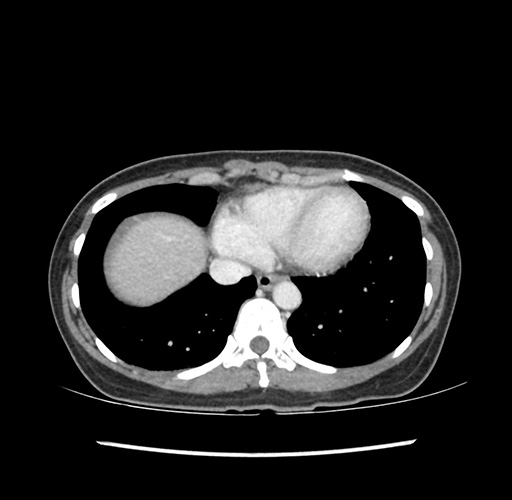

Imaging Analysis

Look through the patient's CT scan to identify any areas of concern for the necessary procedure.

Based on your CT findings, which issue(s) would give reason for "planned slowing down moment(s)" in this case?